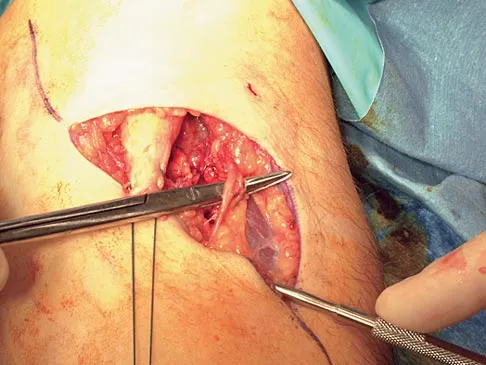

During the anterior approach for repair of a distal biceps tendon rupture, what structure, shown under the scissors in Figure 6, is at risk for injury?